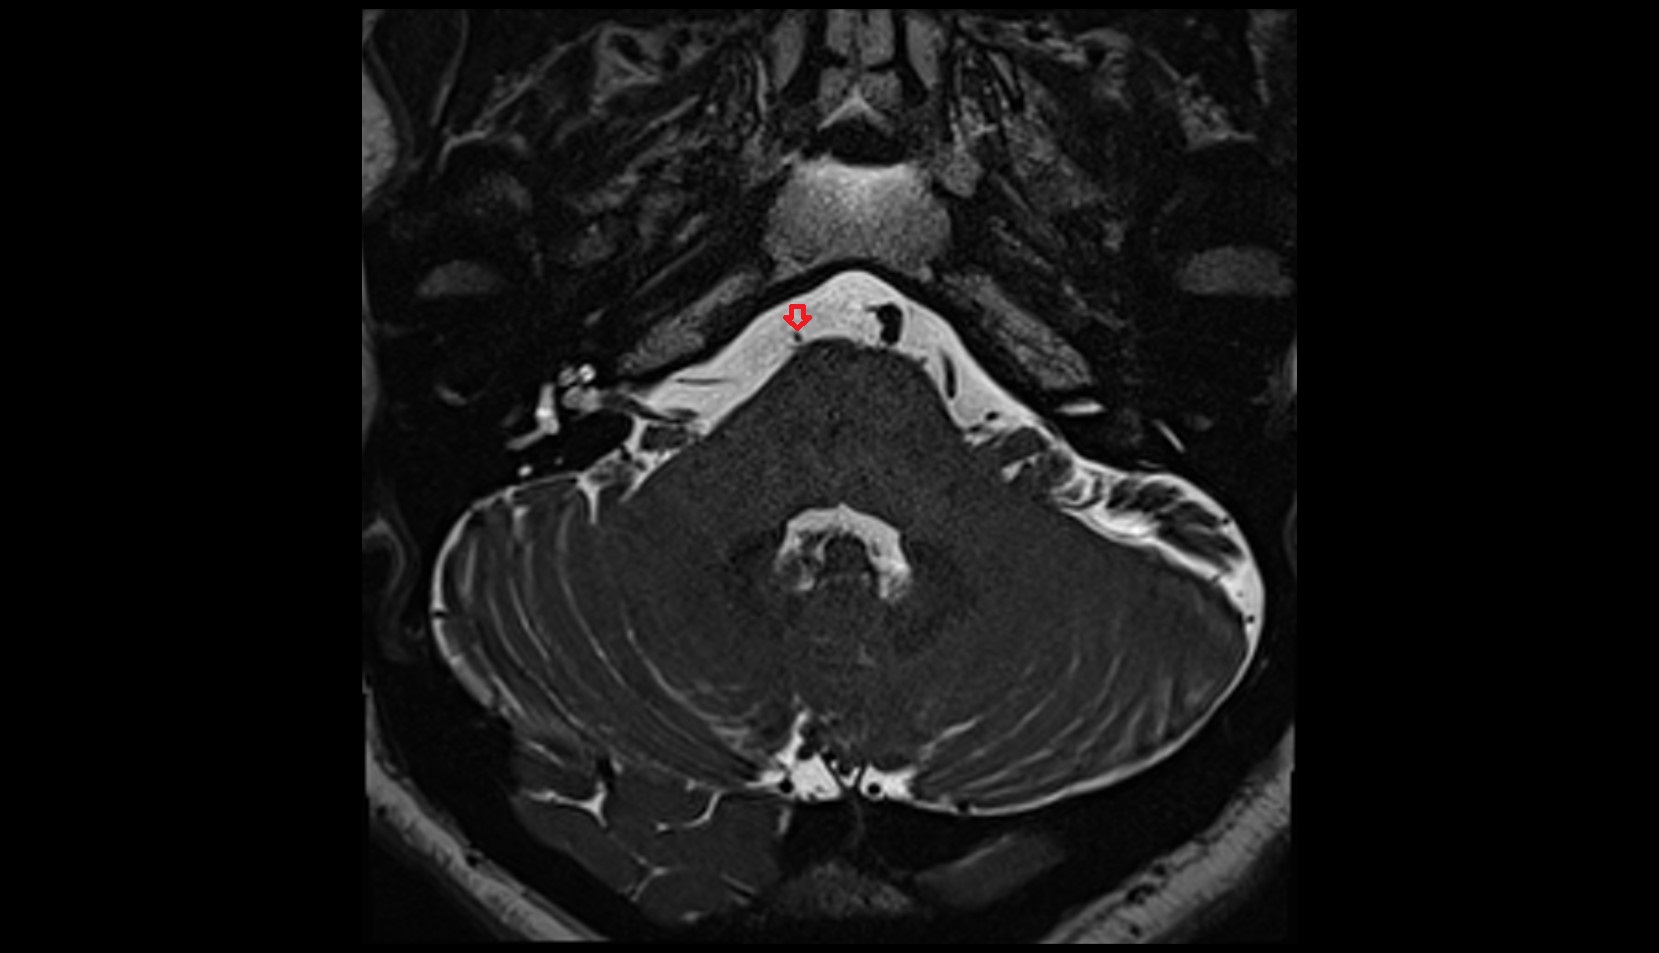

- Peripheral zone of prostate

- Anterior Fibromuscular Stroma of prostate

- Central zone of prostate

- Transitional zone of prostate